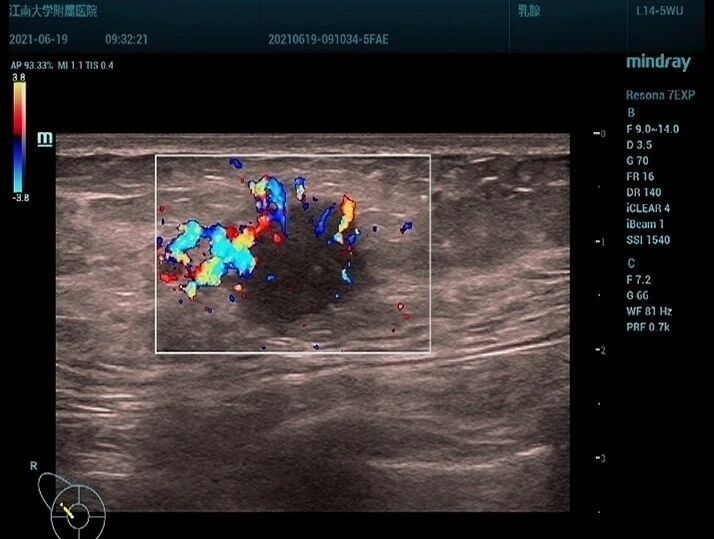

患者,女,63 岁,因右乳肿块一周入院,超声于右侧乳腺 10 点钟方向见一低回声结节,不规则形,边缘模糊(图 1),内部回声不均, CDFI 见较丰富血流信号(图 2), PW 测及高阻动脉血流频谱, RI:0.78 (图 3)。

图 2 CDFI 见较丰富血流信号